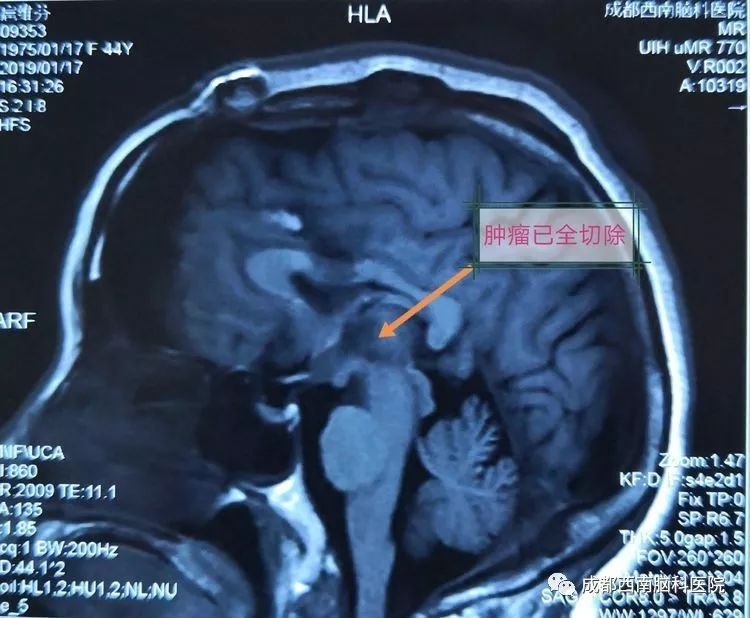

术后复查MRI显示已全部切除